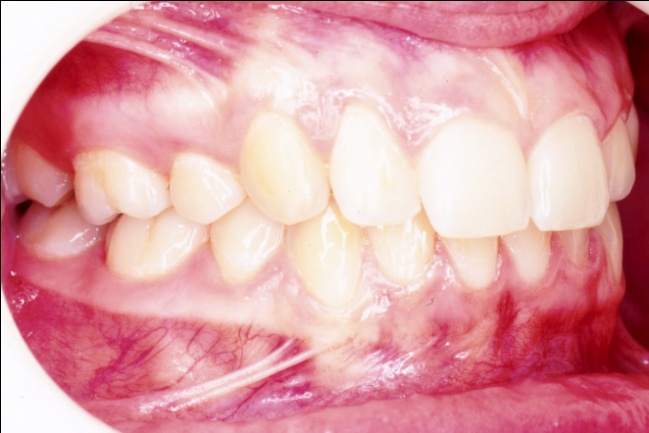

4 - Quand les extractions embellissent… ou enlaidissent

Le changement est spectaculaire : le sourire et le profil sont métamorphosés, avec un effet attendu sur le développement psychologique de l’enfant. Ici, les extractions étaient pleinement justifiées par un profil initial très biprotrusif, permettant une nette amélioration esthétique. Mais appliquée à un profil normal, la même mécanique pourrait avoir l’effet inverse : lèvres rétractées, ourlet naturel perdu et angle nasolabial ouvert, donnant une proéminence excessive au nez.